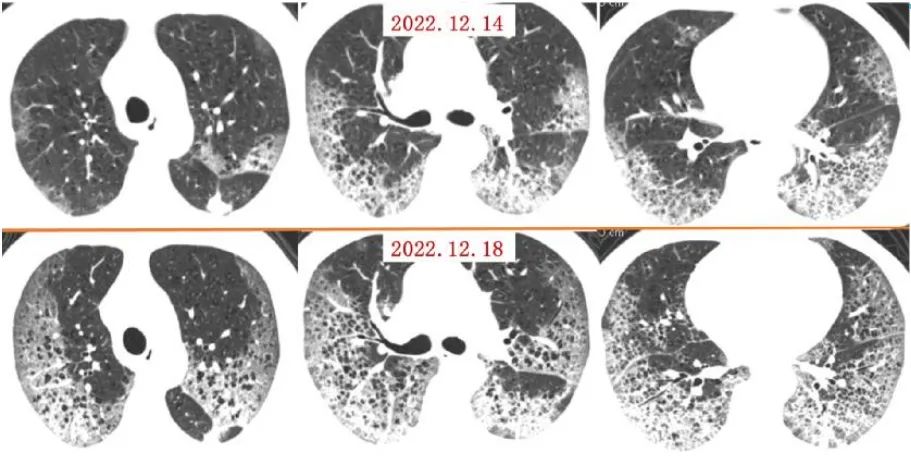

案例一,61歲,女性,確診病例

影像所見:有慢性阻塞性肺疾病病史。2周前受涼后出現(xiàn)發(fā)熱,伴咳嗽、咳痰。入院后給予吸氧,5天后出現(xiàn)口唇紫紺 ,改為BIPAP呼吸機(jī)輔助通氣。12月14日和12月18日,兩肺病灶自肺野外周、下后部向中心和上部迅速擴(kuò)展,表現(xiàn)為“白肺”。